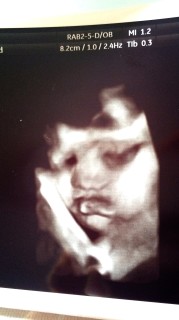

32w5d 頭77㎜お腹280㎜大腿骨58㎜体重1940g。 すくすく育ってます(*^^*) 今回はぺろっと舌を見せてくれました!指もよく動かして元気そうな姿が見られて嬉しいです。今回のエコーで性別がわかったような!?(主人は確信しているので敢えて先生には聞いてません)張りもおさまり赤ちゃんが元気なら退院できると信じて3週間経ちました、34週が節目のようです、あともう少し(^^;)もう少し頑張ろうね。

口元がはっきり映っているので気に入っています。